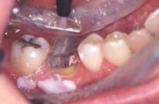

○適応症(写真をご参照ください)は、